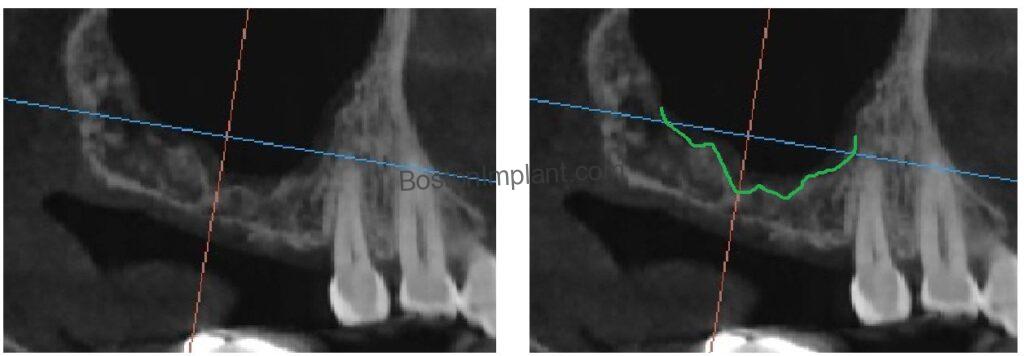

1. An Irregular Sinus Floor To perform a sinus graft, we must delicately lift the Schneiderian membrane—a tissue as thin and fragile as the lining of an eggshell. Think of it like peeling a piece of tape off a delicate surface without tearing it. While we always aim for a smooth, clean detachment (as seen in the left image), the reality of complex anatomy sometimes makes the process look more like the image on the right.

Because this patient’s sinus floor was highly irregular, the procedure required extra precision. This anatomy naturally carries a higher-than-average risk of membrane perforation, making a meticulous approach essential.